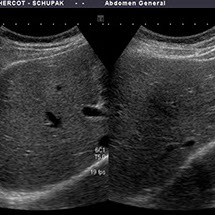

L'échographie est une technique d'imagerie numérique basée sur l'émission et la réception d'ultrasons (comme les radars). Les sons, plus ou moins absorbés ou réfléchis par les structures suivant leur nature, retournent vers la sonde et le signal est transformé en image.

La technique consiste à balayer la structure à explorer avec une sonde qui émet et reçoit les ultrasons, la sonde étant au contact de la peau. Un gel cutané (ne tachant pas, non allergénique) permet de créer une interface directe entre la sonde et la peau évitant l'air qui constitue un obstacle aux ultrasons.

• L’abdomen : foie, vésicule biliaire, reins, rate, pancréas, aorte.